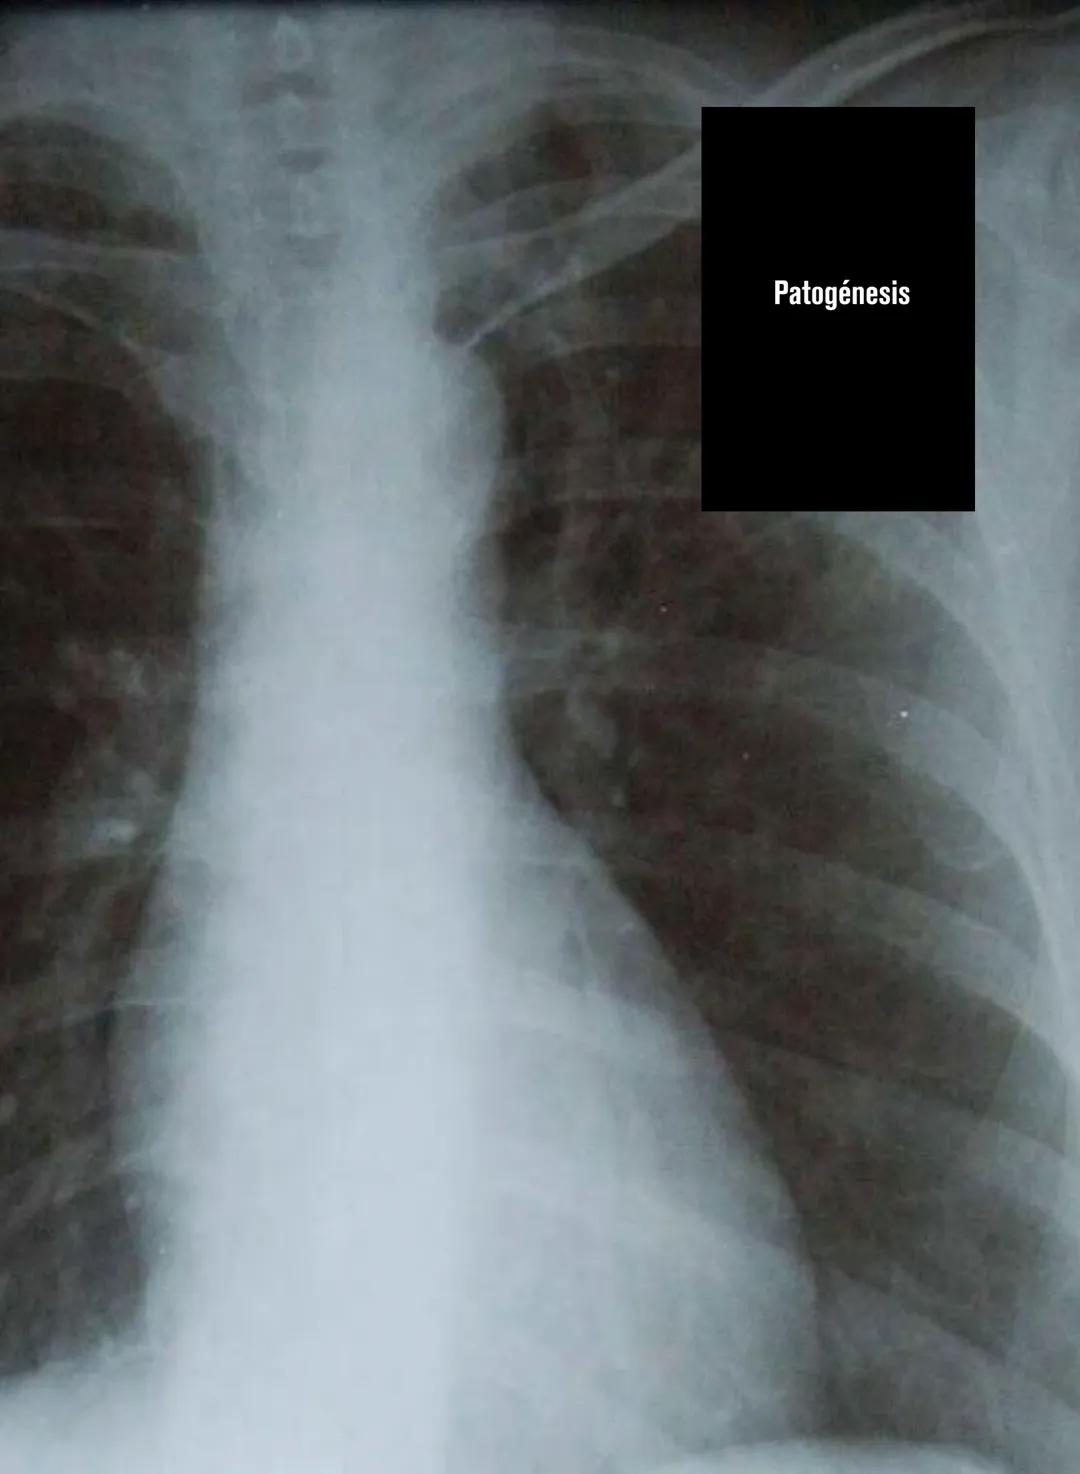

¿Sabías que la tuberculosis es causada por una bacteria súper resistente llamada Mycobacterium tuberculosis o bacilo de Koch? Esta bacteria generalmente ataca los pulmones, causando lo que se conoce como tuberculosis pulmonar, que es el tipo más común que existe.

Los síntomas son bastante específicos y debes reconocerlos: tos con flemas, pérdida de peso, fiebre, sudoración nocturna, cansancio y dolor en el pecho. Lo más preocupante es la hemoptisis (toser sangre), que es una señal de alarma importante.